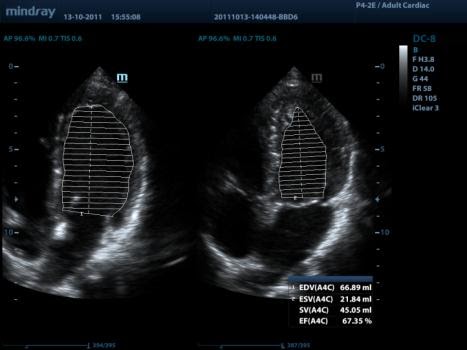

Auto LV (автоматическое измерение левого желудочка)

Простая процедура измерения левого желудочка с функциями автотрассировки и простой ручной коррекции.